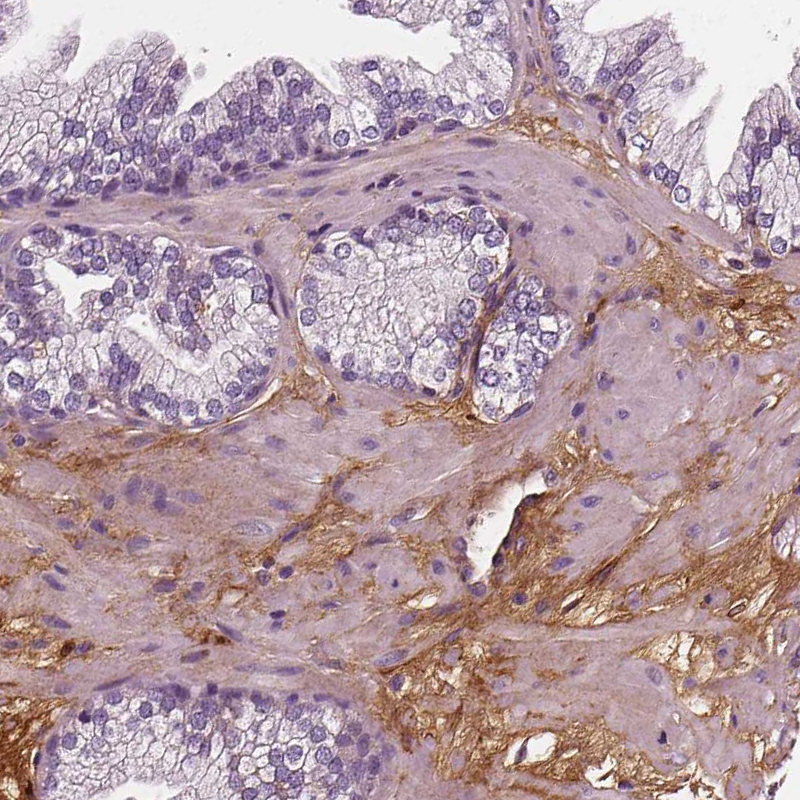

Immunohistochemistry analysis in human cervix, uterine and liver tissues using AMAb90696 antibody. Corresponding FBLN1 RNA-seq data are presented for the same tissues.